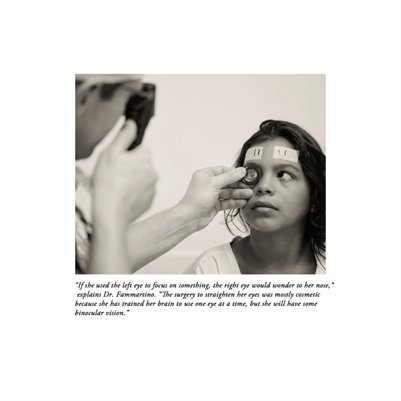

Darkness into the Light. In 2012, The Amazon Project gave eye care to nearly 6000 patients within a 200 kilometer radius of their base in Leticia, Colombia.